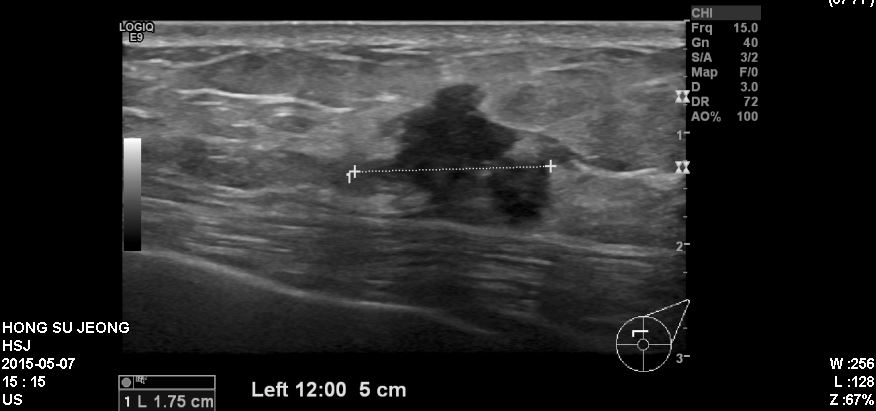

좌측 유방에 만저지는 몽우리로 내원하신 60대 여성분으로 본원에서 만저지는 혹

조직  검사 하였고, 좌측 침윤성 유관암 진단 되었습니다.